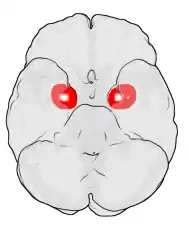

Amygdala

Die Amygdala oder der Mandelkern ist ein paariges Kerngebiet des Gehirns im zur Mitte gelegenen Teil des jeweiligen Temporallappens. Sie ist Teil des limbischen Systems. Der Name der Amygdala (fachsprachlicher Plural: Amygdalae) ist nach ihrem Aussehen aus lateinisch amygdala, dies aus altgriechisch ἀμυγδάλη ‚Mandel(kern)‘, geschöpft. Sie wird auch als Corpus amygdaloideum bezeichnet.